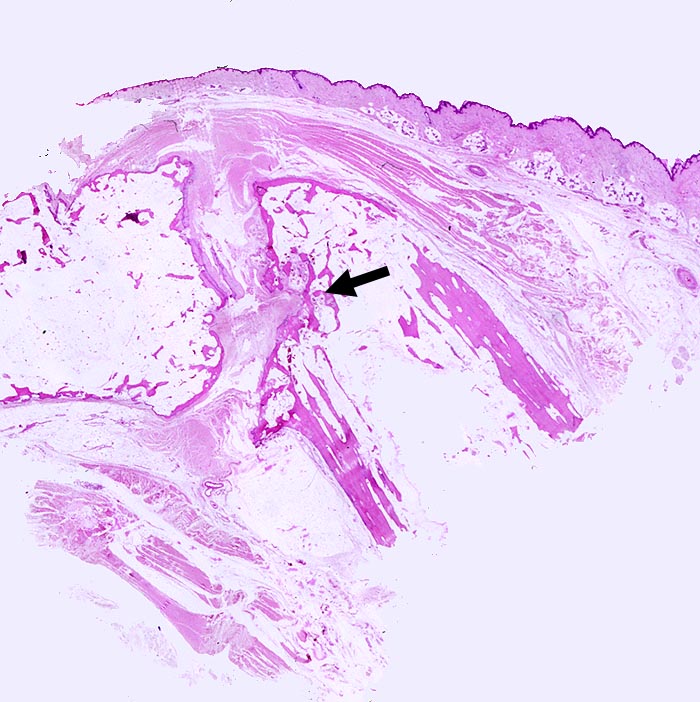

PathoPic – image database / PathoPic ID 194 - Rheumatoide Arthritis Interphalangealgelenk

Rheumatoide Arthritis Interphalangealgelenk

Interphalangealgelenk mit sehr unregelmässiger Gelenkfläche und praktisch fehlendem Knorpel. Im Gelenkspalt bindegewebiger Pannus.

Dieser zerstört an einer Stelle die Gelenkfläche und dringt in die Spongiosa ein.